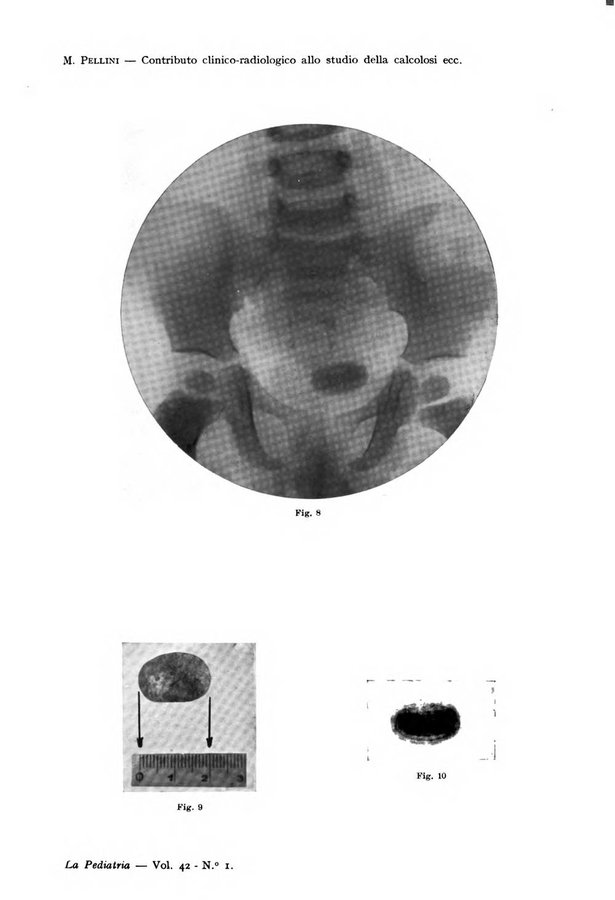

- La pediatria periodico mensile indirizzato al progresso degli studi sulle malattie dei bambini